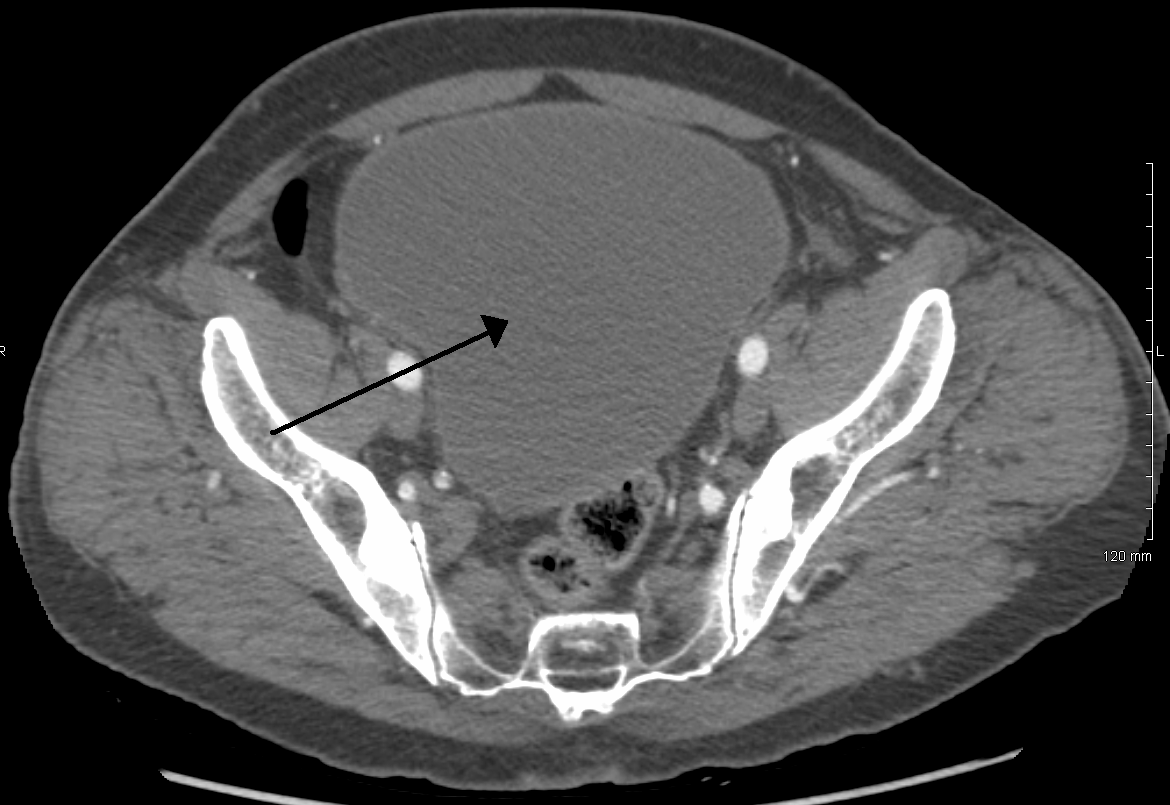

뇨류를 분석하면 배뇨 이상의 유형을 판단하는 데 도움이 될 수 있다. 방광 초음파를 통해 흔히 진단되는 것들로는 느린 속도의 뇨류, 간헐적인 뇨류, 배변 후에도 방광 내에 잔재하는 상당한 양의 오줌이 있다. 정상 시험 결과는 초당 최고 20ml~25ml의 뇨류 속도를 보인다. 배뇨 후 남은 소변이 50ml를 초과하는 경우 상당한 양으로 간주되며 요로감염증이 재발할 가능성을 높인다. 60세 이상의 성인의 경우 50ml~100ml의 잔여 소변은 방광의 용적을 증대시킨다. (정상 용적은 400ml~600ml)

만성 요폐의 경우 방광 초음파 검사에서 방광 용량의 대규모 증가를 보일 수 있다. 비신경성 만성 요폐는 표준화된 정의가 없지만, 300ml 이상의 소변량이 비공식적인 지표로 사용될 수 있다.[8] 요폐 진단은 6개월 동안 진행되며, 6개월 간격으로 2번의 소변량 측정이 이루어진다. 측정 결과는 배뇨 후 잔뇨량(PVR)이 300ml 이상이어야 한다.[8]